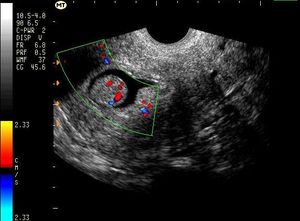

SAG Uterus (Transvaginal) Endometrial PolypPublished: June 15th 2011 | Updated: